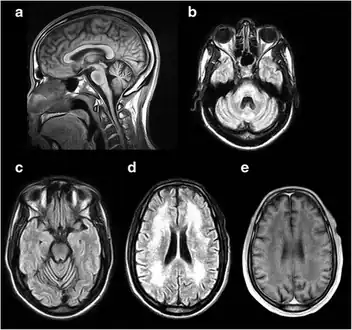

a-e) MRI of the brain demonstrating characteristic findings in DRPLA

To quantify the extent of the disease, an MRI, EEG and neuropsychological testing are recommended. Seizures are treated with anticonvulsants and psychiatric disturbances with psychotropic medications. Physical therapy has also been recommended to maintain function as the condition progresses and occupational therapy to focus on activities of daily living, advice for carers and adaptation to the environment.